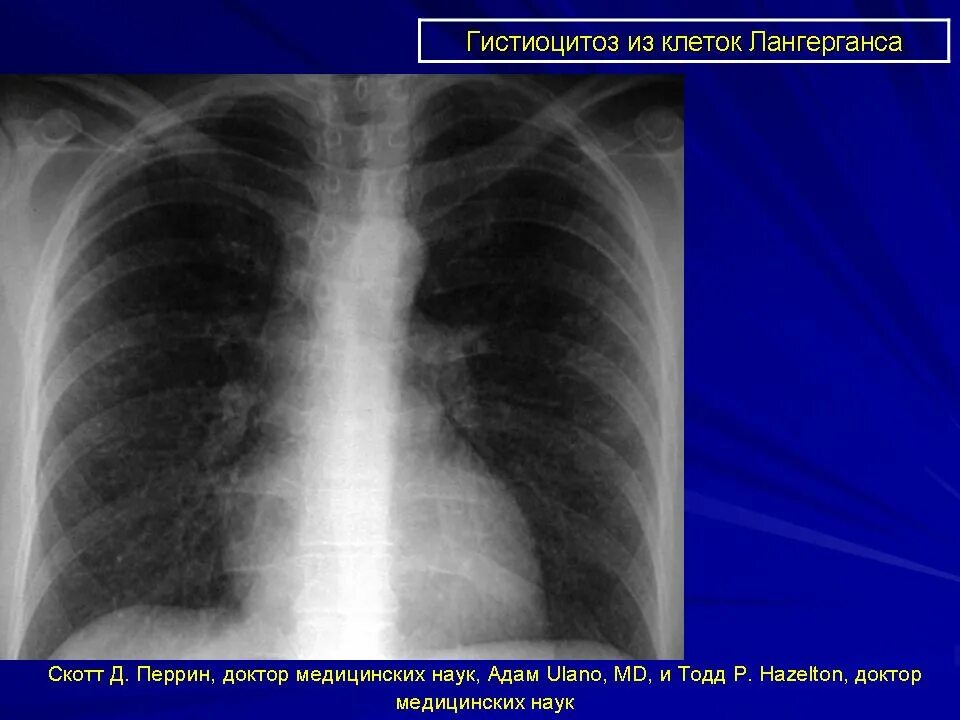

Гистиоцитоз лимфатических узлов что это